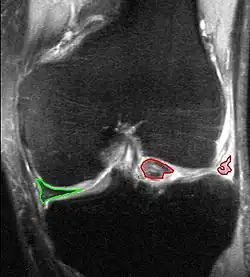

X-ray images (normally during weightbearing) can be obtained to rule out other conditions or to see if the patient also has osteoarthritis. The menisci themselves cannot be visualised with plain radiographs. If the diagnosis is not clear from the history and examination, the menisci can be imaged with magnetic resonance imaging (an MRI scan). This technique has replaced previous arthrography, which involved injecting contrast medium into the joint space. In straightforward cases, knee arthroscopy allows quick diagnosis and simultaneous treatment. Recent clinical data shows that MRI and clinical testing are comparable in sensitivity and specificity when looking for a meniscal tear.

A meniscal tear can be classified in various ways, such as by anatomic location or by proximity to blood supply. Various tear patterns and configurations have been described.[12] These include:

- Radial tears

- Flap or parrot-beak tears

- Peripheral, longitudinal tears

- Bucket-handle tears

- Horizontal cleavage tears

- Complex, degenerative tears

These tears can then be further classified by their proximity to the meniscus blood supply, namely whether they are located in the “red-red,” “red-white,” or “white-white” zones.